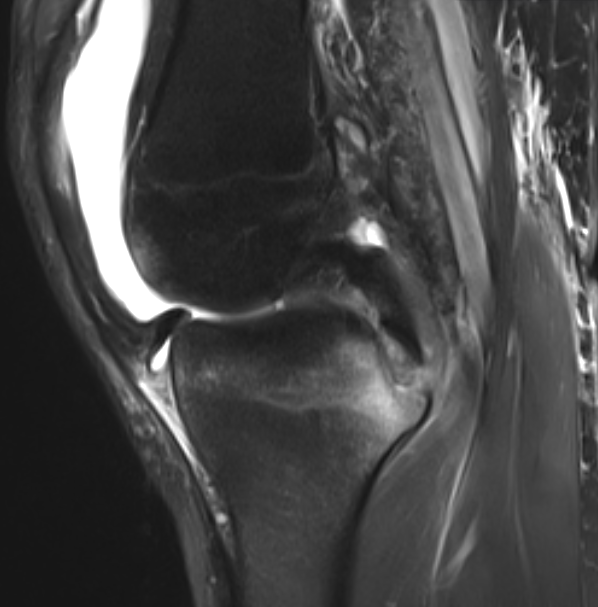

3. PCL avulsion injury